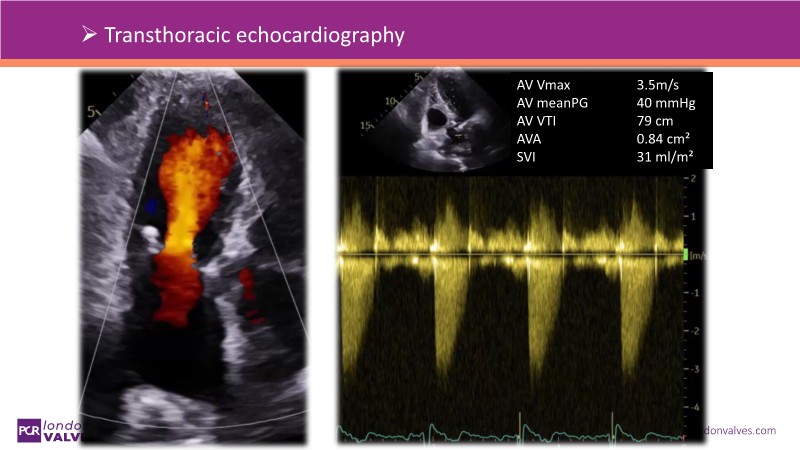

This session addresses emerging topics in structural heart disease by examining patient-centered solutions such as EVOQUE transcatheter tricuspid valve replacement (TTVR) and SAPIEN transcatheter heart valve-in-heart valve (THV-in-THV) procedures. It covers the latest data from Europe on redo TAVI, lifetime management strategies beginning with initial prosthesis planning, evolving patient selection for TTVR, and features an educational live case alongside expert panel discussions on procedure safety and efficacy.

- To understand the latest considerations and techniques for redo TAVI and get exposed to the latest data from Europe

- To learn how to maximise the benefits of TAVI with a lifetime management strategy that starts with the planning of the first prosthesis